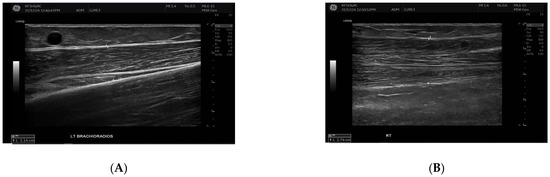

Exploratory Assessment of Muscle Thickness and Stiffness Around Arteriovenous Fistulas Using Shear Wave Elastography

Background/Objectives: Muscle thickness and stiffness near the arteriovenous fistula (AVF) site may influence vascular access function in hemodialysis patients. This exploratory study aimed primarily to describe differences in muscle thickness and stiffness between the AVF-bearing and contralateral limbs, and secondarily to examine [...] Read more.

Background/Objectives: Muscle thickness and stiffness near the arteriovenous fistula (AVF) site may influence vascular access function in hemodialysis patients. This exploratory study aimed primarily to describe differences in muscle thickness and stiffness between the AVF-bearing and contralateral limbs, and secondarily to examine whether these parameters were associated with AVF maturation. This study aimed to compare these muscle parameters between the AVF and contralateral sides and to evaluate their relationship with AVF maturation status. Methods: Thirty participants undergoing hemodialysis were included, comprising 22 with mature AVFs and 8 with non-mature AVFs. Ultrasound examinations measured muscle thickness and stiffness using Shear Wave Elastography (SWE) of the biceps brachii and brachioradialis muscles. Volume flow was recorded in the draining vein and feeding artery. Statistical analyses included paired comparisons, group comparisons, Pearson correlations, and multiple linear regression models. Results: Brachioradialis thickness was significantly reduced on the AVF side compared with the contralateral side (p = 0.013, Cohen’s d = –0.95), particularly in forearm (radiocephalic) fistulas (Wilcoxon p = 0.014, Cohen’s d = –0.95), indicating localized muscle atrophy. No significant side-to-side differences were found for biceps brachii thickness or for stiffness in either muscle (all p > 0.1). Comparisons between mature and non-mature AVF groups showed no significant differences in muscle parameters on the AVF side (all p > 0.4). Conclusions: AVF may lead to asymmetric muscle changes, especially a reduction in brachioradialis thickness, regardless of maturation status, which could affect forearm function. Nevertheless, muscle thickness and stiffness do not appear to predict AVF maturity or vascular access success directly. Full article

Show Figures

Figure 1